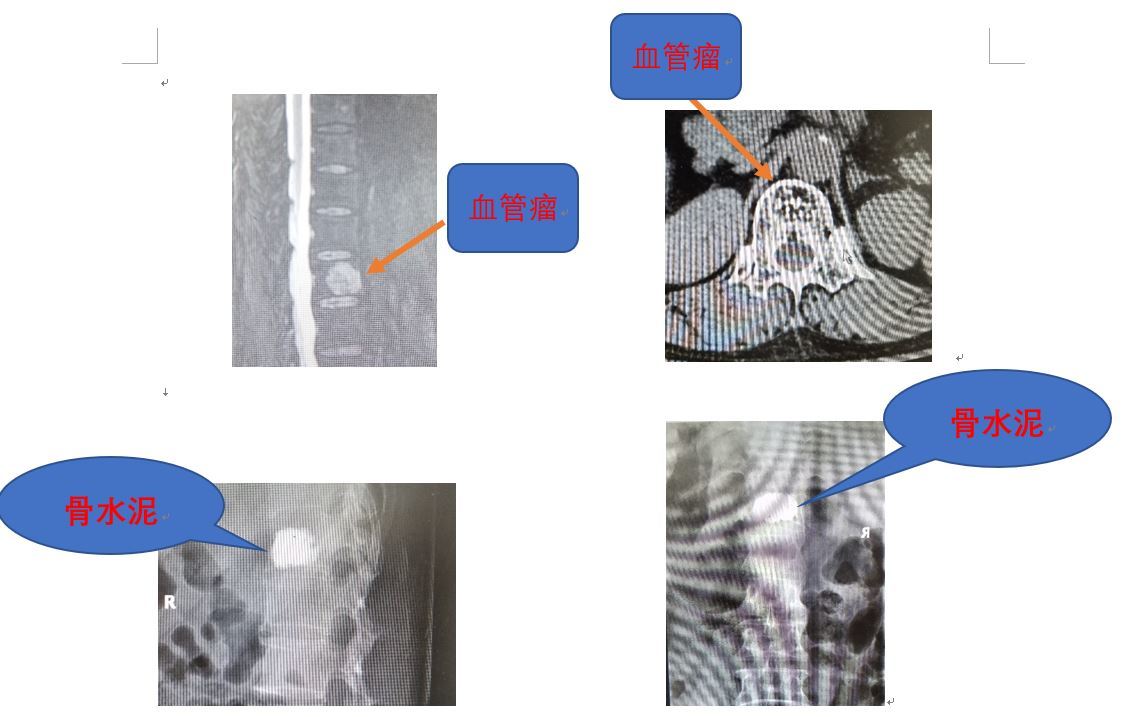

骨泥成型術用於脊椎血管瘤 55歲黃太太住在台北 因為長年腰痛看遍台北各大知名醫院仍然無效 經朋友介紹來莊醫師門診 經過詳細核磁共振檢查發現 腰椎第二節有一個脊椎血管瘤 莊醫師以骨泥成型術將病灶封閉 黃太太的腰痛從此遠離了 許多醫師對

椎体血管瘤的骨水泥注射治疗 上海六院推荐的临床一线方法

骨血管瘤- · 脊椎退化 是人類的宿命,加上壽命延長,因脊椎退化所出現的 神經痛 ,如頭、頸、胸、背、下背痛以及四肢關節之麻痛無力,成為診間病人常見的問題。 目前健保提供之治療,包括口服止痛藥、復健、中醫治療等,還有坊間推拿、 整脊 等另類療法,一旦療效不佳,手術似乎成為唯一的選擇。 在此,先介紹神經痛的成因。 首先,脊椎骨不同於四肢骨骼,其中有一空腔骨血管瘤介紹 ‹ › 骨血管瘤系錯構瘤,是一種良性腫瘤。 可以發生於身體的各個部位,也可發生於骨內,但後者遠比發生於其他部位的血管瘤少見。 據國內資料統計,脊柱骨血管瘤約占原發性脊柱瘤的3%~81%,但臨床上檢出率較低,原因可能是:骨血管瘤為良性,生長緩慢,早期患者無癥狀或癥狀輕微,患者不就醫,故不被發現。 晚期患者溶骨性破壞改變顯著時

脊髓用成形骨泥 tecres 衛署醫器輸字 第號 椎體撐開術 心動停止、血管梗塞、肺 栓塞、血壓一時下滑、血 種、深處感染、短時間心 跳不規則、突然死亡、骨 泥在椎體外的擴散 1健保骨水泥溫度較高且 凝固時間較快 2健保骨水泥多用在四肢 骨頭並不適 · 肝血管瘤是一種常見的肝臟良性腫瘤, 對患者來說很重要的就是日常飲食, 科學的食療對病情很有幫助, 一定要忌酒, 不要吃煎炸食品, 多吃蔬菜水果, 注意飲食的衛生。 一、 肝血管瘤的飲食方案如下: 1、絕對禁酒。 2、選用去脂牛奶或優酪乳。 3、每天吃的雞蛋黃不超過2個。 4、忌用動物油;植物油的總量也不超過克。 5、不吃動物內臟 (即下水、下貨至4公分,而且需移除腰椎部分之脊椎椎板骨,有時可能發生傷口感染、神經損傷、 硬脊髓膜外出血或伴隨著不穩定脊椎等併發症。 另一種手術方式為經皮內視鏡椎間盤切除術(Percutaneous Endoscopic Lumbar Diskectomy,簡稱PELD),其為一種創新脊椎微創手術,使用直徑07